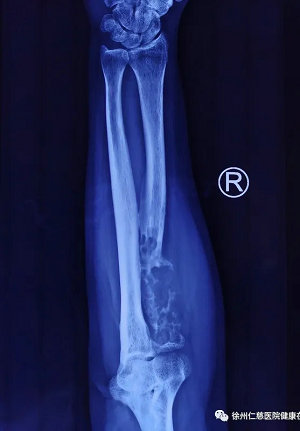

患者3年前发现右前臂疼痛,近期体检时才发现是右桡骨骨肿瘤。

患者女性,52岁,3年前开始发现右前臂疼痛,一直未引起重视,坚持劳动,近期在体检时才发现是右桡骨骨肿瘤,于是慕名前来betway在线登陆治疗,找到关节科邱东新副主任医师;邱医生经过详细的检查,认为患者骨肿瘤侵犯骨质节段较大,必须手术,治疗分为两阶段进行。第一阶段先行病理活检,明确肿瘤性质;病理结果提示肌周细胞肿瘤,低度恶性;在第二阶段,行彻底手术,瘤段需要扩大切除,而切除后如何最大程度地保留患肢的功能,是需要仔细设计和规划的。

关节科张传开主任、邱东新医生联合大骨科主任张贯林副院长,反复仔细研究患者病情,分析影像资料,考虑肿瘤主要集中在右桡骨近端,长度达8cm,加上扩大切除部分,整个桡骨需要切除的长度在13cm,骨骼缺损的范围太大,如果无法重建恢复骨骼形态,患肢功能将严重缺失;考虑患者相对年轻,还有日常生活功能的要求,医生团队决定尽最大可能保留肢体形态与功能,邱医生与患者及家属反复多次沟通后,最终决定为患者进行高难度的右桡骨骨肿瘤切除+3D打印假体置换手术。